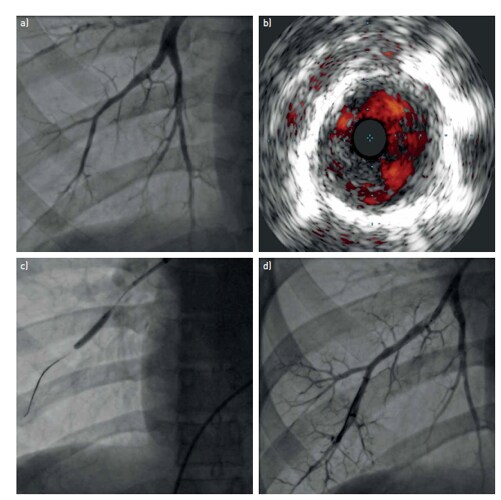

Pulmonary arterial imaging before and after percutaneous balloon pulmonary angioplasty (BPA).

a) Pre-procedure pulmonary angiogram demonstrating an intra-arterial fibrous “web” lesion; b) the corresponding intravascular ultrasound image showing the intravascular filling defect; c) the BPA balloon in place; d) pulmonary angiogram after the BPA procedure, showing the patent arterial lumen. Image from Lang et al 2017.1